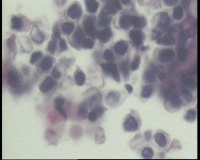

| 一般病史 | 彩超:盆腔可见囊实性回声,囊性为主,大小约5.0x3.7厘米,其内可见分隔回声,部分分隔内回声不纯净,形态欠规整 | ||||

| 标本名称 | 腔镜下右侧卵巢囊肿手术 | ||||

| 大体所见 | 囊壁样组织5.5x5.0厘米,4.5x2.5厘米2块,壁厚0.1-0.2lm,囊壁大部分光滑,局灶见0.7x0.5x0.3厘米淡黄色突起组织,另见淡黄色、肉粉色质软组织2.8厘米一堆。 | ||||